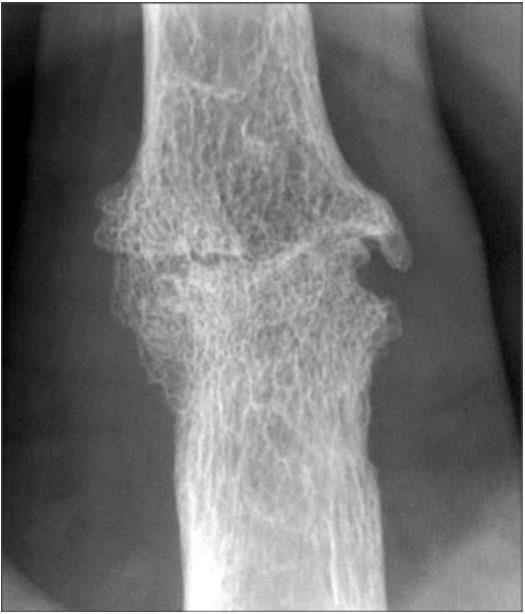

Рис. 17. Рентгенограмма пястно-фалангового сустава больной РА, III стадия, боковая проекция сустава, 6-кратное увеличение рентгеновского изображения:

а — необработанное изображение. Резко выраженный диффузный остеопороз с исчезновением костной ткани, трабекул, множественные глубокие краевые дефекты костной ткани (эрозии) с размытыми краями, исчезновение суставной щели; б — обработка методом амплитудного рельефа. Метод амплитудного рельефа объемно выявляет помимо слабовыраженного трабекулярного рисунка эрозии (узуры) в виде кратерообразных ступенчатых углублений